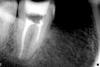

Михалыч Опубликовано 12 марта, 2008 Поделиться Опубликовано 12 марта, 2008 альтернатива РФ - нормальная эндодонтия. Потом на вашем РФ вырастет сиська и его придется выпиливать из челюсти.А вот что прикажете вот с этим делать?Или тоже хирургам отдавать?Более двух часов возился с медиальными, в итоге вот что:А это на стадии "крезофена", отпустил домой! Завтра буду пломбировать!В итоге если будут проблемы, то и 47 и 46 под гемисекцию!Вы что посоветуете? Ссылка на комментарий

АНРОША Опубликовано 12 марта, 2008 Поделиться Опубликовано 12 марта, 2008 А вот что прикажете вот с этим делать?Или тоже хирургам отдавать?Более двух часов возился с медиальными, в итоге вот что:А это на стадии "крезофена", отпустил домой! Завтра буду пломбировать!В итоге если будут проблемы, то и 47 и 46 под гемисекцию!Вы что посоветуете?Это перелечивание после РФ? Ссылка на комментарий

Михалыч Опубликовано 13 марта, 2008 Поделиться Опубликовано 13 марта, 2008 В том то и дело что ни в первом не во втором случае зубы не резорцинены. А вот как без него сейчас, ума не приложу. Склоняюсь к гемисекциям, иначе ничего гарантировать пациенту не смогу. Ссылка на комментарий

NataLee Опубликовано 13 марта, 2008 Поделиться Опубликовано 13 марта, 2008 В том то и дело что ни в первом не во втором случае зубы не резорцинены. А вот как без него сейчас, ума не приложу. Склоняюсь к гемисекциям, иначе ничего гарантировать пациенту не смогу.Во втором случае я бы рекомендовала удаление сразу. Помимо проблем на верхушках, фуркация, как мне кажется, истончена. А значит, ортопедическое восстановление под большим вопросом. Если так, то любая попытка терапии есть продление агонии зуба.Но это только мое ИМХО Ссылка на комментарий

Doc Опубликовано 13 марта, 2008 Поделиться Опубликовано 13 марта, 2008 А вот что прикажете вот с этим делать?Или тоже хирургам отдавать?Более двух часов возился с медиальными, в итоге вот что:В итоге если будут проблемы, то и 47 и 46 под гемисекцию!Вы что посоветуете? Михалыч, ну сделаете Вы этому зубу гемисекцию. А дальше что? Шестого зуба нет, будете тянуть мост на семь-пять? А пять живой вроде (и восьмой вроде тоже живой)? А надежность такого моста? А смысл тогда? Давайте идти от конца. Какую ортопедию Вы там предполагаете делать? А вот после ответа на этот вопрос думать уже что делать с седьмым. Ссылка на комментарий

Bier Опубликовано 15 марта, 2008 Поделиться Опубликовано 15 марта, 2008 А вот что прикажете вот с этим делать?Или тоже хирургам отдавать?Более двух часов возился с медиальными, в итоге вот что:А это на стадии "крезофена", отпустил домой! Завтра буду пломбировать!В итоге если будут проблемы, то и 47 и 46 под гемисекцию!Вы что посоветуете? первый - удалять, Док объяснил почему. Но допустим был бы 6й зуб. Либо предложить пациенту негарантированное лечение, либо гарантированно поставить туда имплантат. Резорцин ведь не решит проблемы, а только создаст их при удалении зуба. Гемисекция тоже метод сомнительный. ну а второй однозначное удаление. Ссылка на комментарий

Bier Опубликовано 16 марта, 2008 Поделиться Опубликовано 16 марта, 2008 У нас в клинике один канал получается в среднем 1200 руб. Конечная цель протезирование МКХотя мы не придерживаемся положительных взглядов в протезировании комбинации имплантов и живых зубов ну сделайте МК на этот зуб, только не под мост, если пациент согласится на негарантированное лечение, хотя мне кажется, что на мезиальном корне уже есть гранулема. А что применение РФ даст вам внутреннее убеждение о надежности такой работы или гранулема изчезнет?По хорошему, если эндо сделать никак не получается, я бы этот зуб удалил. Ссылка на комментарий